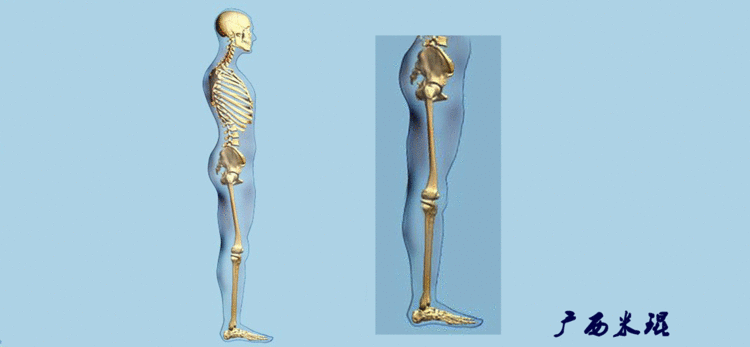

(2)机械轴机械轴是连接近端和远端关节中心点的直线。

机械轴要分前后位及侧位,站立前后位(也就是冠状面)股骨头中心与踝关节中心的连线通过膝关节中心,这是下肢的机械轴线,也就是下肢力线,常说Mikulicz线。冠状面的力线评估在临床工作中最常用、最基础、最重要。

站立侧位(矢状面)股骨头中心与踝关节中心的连线也通过膝关节中心,这也是下肢的机械轴线,这也是下肢力线。

(3)垂直轴也就是下肢的负重轴,它是身体的纵轴线,与地面垂直,由于双髋比双踝的距离宽,所以垂直轴与下肢力线(机械轴)存在3°的外翻。

开始接触时可能我们对这些轴有点混乱,通过下面的这张图片就能清楚的了解下肢几个轴之间的关系。